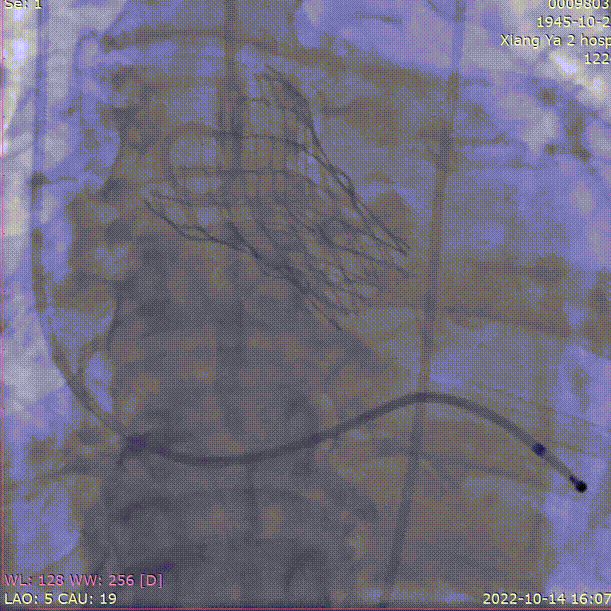

手术关键步骤

A.主动脉根部造影

D. 瓣膜释放后造影